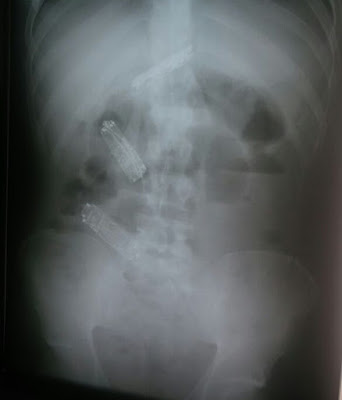

No entanto, depois de uma semana, ele não obteve sucesso em seu plano e estava sentindo fortes dores em sua barriga. Ele foi encaminhado à Santa Casa de Presidente Bernardes, onde um exame de raios-X constatou os três aparelhos em seu estômago.